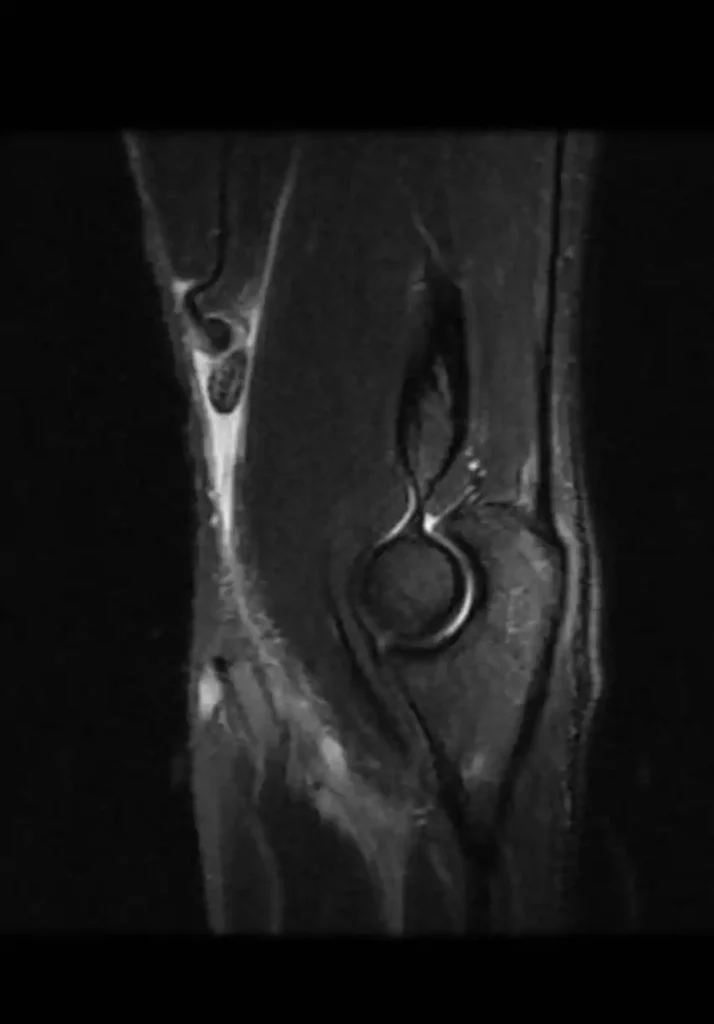

Exames de imagem podem ser solicitados para confirmação a ruptura do bíceps distal.

O ultrassom pode ser solicitado, mas o melhor exame é a ressonância magnética (foto abaixo).

A ressonância nos dá com mais precisão a qualidade do tendão rompido, sua retração e define melhor outras alterações que podemos encotrar associadas a ruptura do bíceps distal como bursite e aumento de líquido.